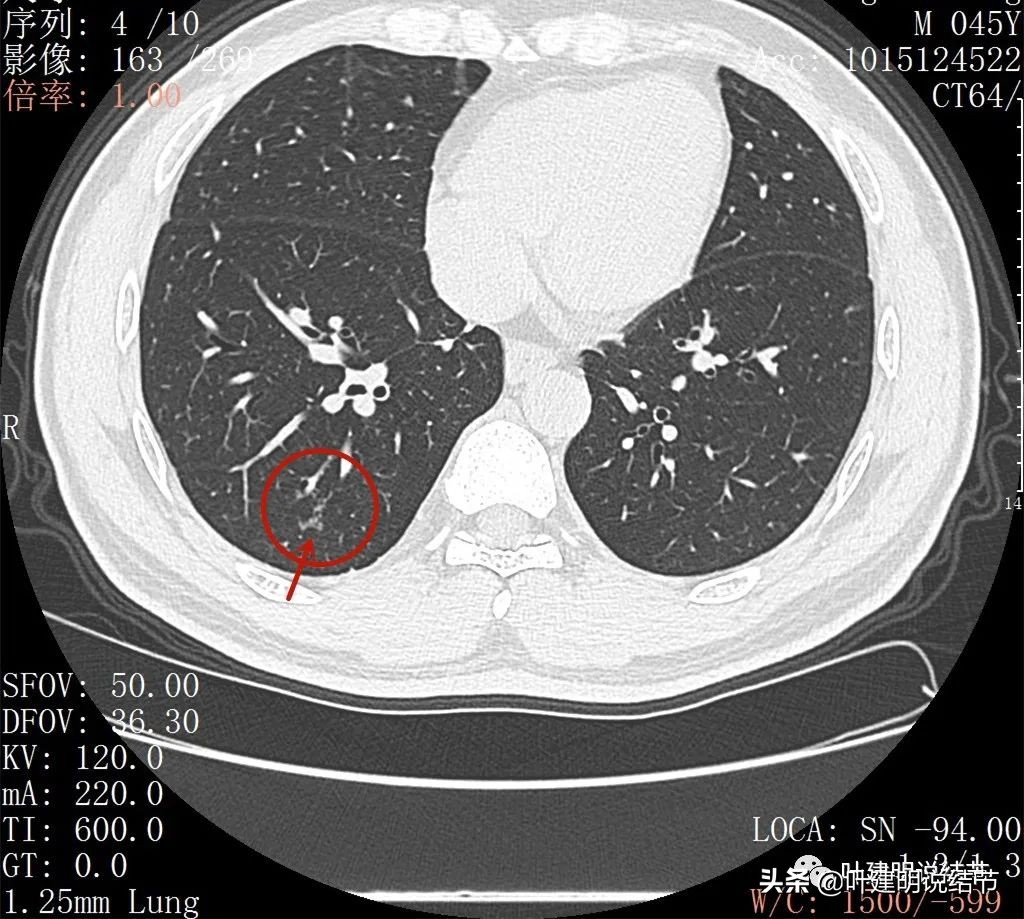

此层见病灶边缘显糊

病灶显模糊,感觉过于散在了些

病灶形散,密度低